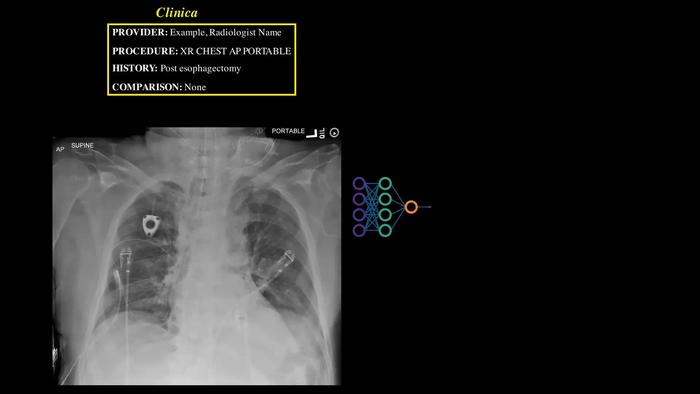

Unlike conventional narrow AI systems that are limited to identifying specific conditions, Northwestern’s system employs a comprehensive approach. By evaluating the entirety of the X-ray or CT scan, it can automatically generate a report that is approximately 95% complete. This personalized report assists radiologists, who can fine-tune the output to suit each patient’s unique situation. The ability of the AI to deliver tailored reports significantly lightens the workload for radiologists, allowing them to focus on critical interpretations and decisions.

The immediate clinical applications of this technology are potentially life-saving, particularly in emergency situations where timely diagnostics are crucial. The AI actively monitors reports for urgent conditions like pneumothorax, signaling the presence of dire needs before a radiologist has the opportunity to examine the images. This immediate flagging system serves not only to enhance the efficiency of the radiology department but also to ensure that patients receive the necessary care without unnecessary delays—a critical factor in life-and-death situations.